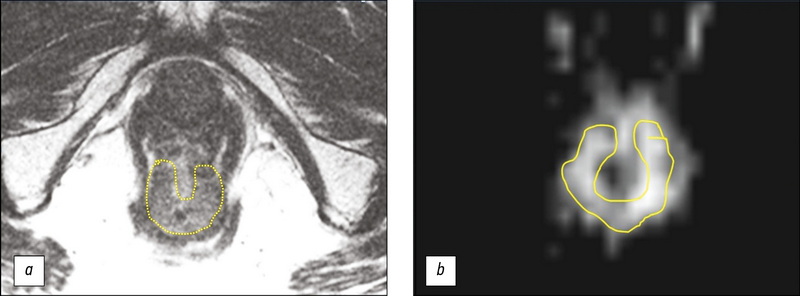

Diagnosis of solitary eosinophilic granuloma by CT, MRI, and 18F-FDG PET/CT: two clinical cases

This paper presents two clinical cases of eosinophilic granuloma of bone diagnosed by CT, MRI, and 18F-FDG PET/CT. In both cases the patients were admitted to the clinic with suspected primary malignant bone tumor and the diagnosis of a solitary eosinophilic granuloma was made based on the results of comprehensive radiological diagnostic examination and histological verification. Solitary eosinophilic granuloma of bone is an infrequent condition, occurring in less than 1% of cases of skeletal tumor masses. The most common eosinophilic granuloma is found in the parietal and frontal bones of the skull and is an osteolytic volumetric mass that gradually increases in size. Although most bone tumors can be detected by radiography, computed tomography is preferred, primarily because of its superior ability to detect cortical bone destruction. The diagnostic accuracy of computed tomography and magnetic resonance imaging may be different. The combined use of radiological and radionuclide methods allows us to narrow the spectrum of differential diagnosis. Unfortunately, relatively low specificity of existing radiological diagnostic studies in most cases does not allow to establish a precise diagnosis, and biopsy with subsequent pathological examination remains the method of choice. These clinical observations demonstrate the need to include eosinophilic granuloma in the differential diagnosis when a solitary osteolytic focus is detected.